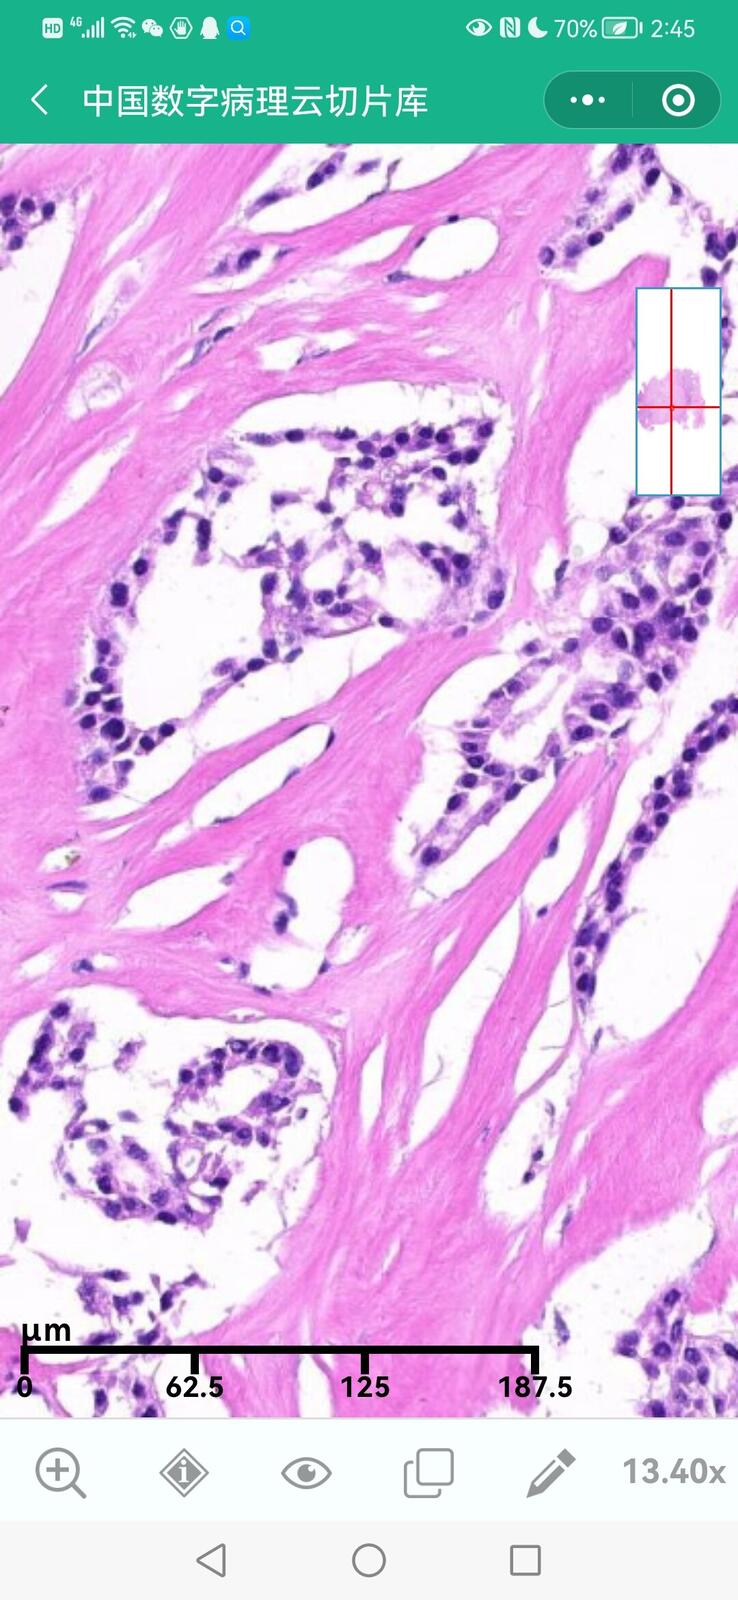

乳腺黏液性囊腺瘤伴导管内癌

乳腺多形性脂肪肉瘤

乳腺叶状囊肉瘤

乳腺分泌性癌(29岁)